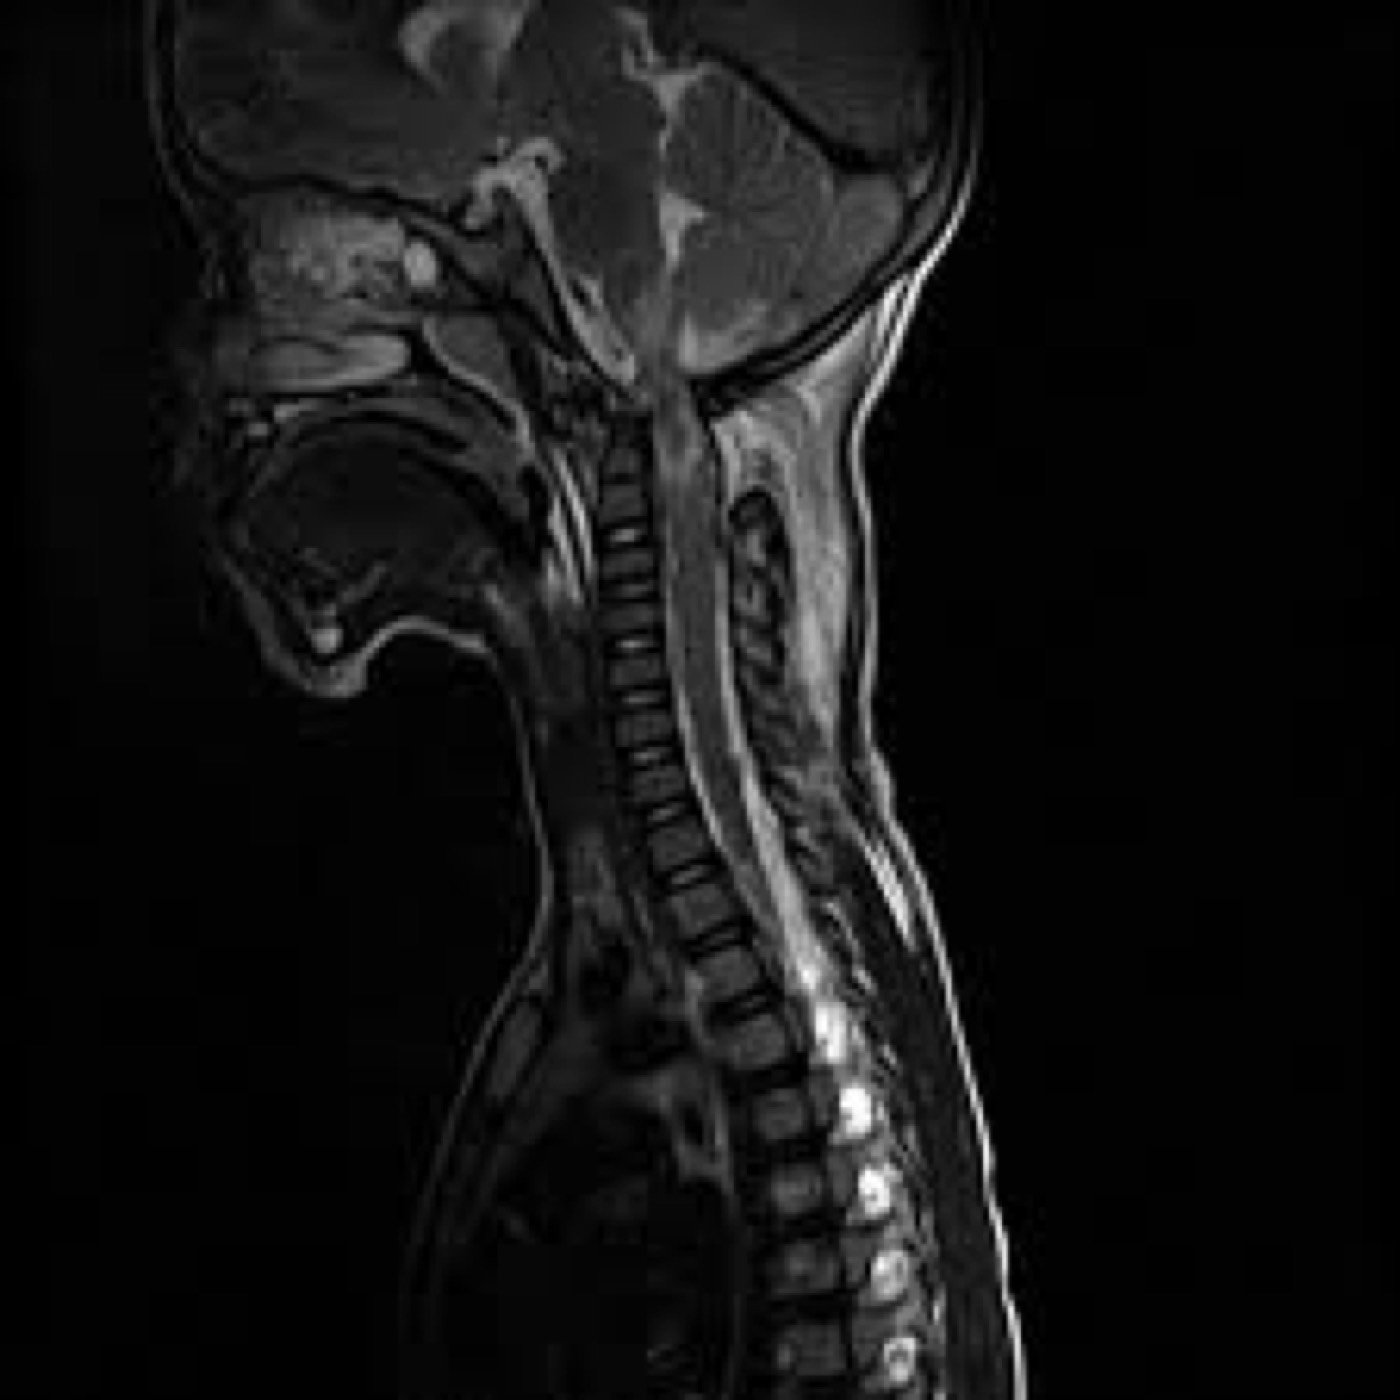

Contributor: Aaron Lessen, MD Educational Pearls: The cause of Alzheimer's disease is multifactorial, but the most widely suspected mechanism is the amyloid cascade hypothesis: Beta-amyloid proteins accumulate in the central nervous system, forming plaques that impair neuronal function. In recent years, advances have led to the development of targeted therapies with monoclonal antibodies. These drugs: Work by degrading amyloid plaques Slow the rate of cognitive decline and disease progression Have major side effects, most notably the development of amyloid-related imaging abnormalities (ARIA) ARIA may present as edema, effusion, or microhemorrhages, which are only detectable on MRI Symptoms can include headache, vertigo, or focal neurologic deficits that mimic stroke For patients presenting to the emergency department with stroke-like symptoms, it is important to consider whether they have a history of Alzheimer's disease and whether they are taking these medications. This guides decisions about imaging and treatment: The work-up may require MRI, which can delay thrombolytic or endovascular therapy in patients with true strokeConversely, treating a patient with ARIA using thrombolytics increases the risk of bleeding and other complications References Ebell MH, Barry HC, Baduni K, Grasso G. Clinically Important Benefits and Harms of Monoclonal Antibodies Targeting Amyloid for the Treatment of Alzheimer Disease: A Systematic Review and Meta-Analysis. Ann Fam Med. 2024 Jan-Feb;22(1):50-62. doi: 10.1370/afm.3050. PMID: 38253509; PMCID: PMC11233076. Ma C, Hong F, Yang S. Amyloidosis in Alzheimer's Disease: Pathogeny, Etiology, and Related Therapeutic Directions. Molecules. 2022 Feb 11;27(4):1210. doi: 10.3390/molecules27041210. PMID: 35209007; PMCID: PMC8876037. Perneczky R, Dom G, Chan A, Falkai P, Bassetti C. Anti-amyloid antibody treatments for Alzheimer's disease. Eur J Neurol. 2024 Feb;31(2):e16049. doi: 10.1111/ene.16049. Epub 2023 Sep 11. PMID: 37697714; PMCID: PMC11235913. Summarized by Ashley Lyons, OMS3 | Edited by Ashley Lyons and Jorge Chalit, OMS4 Donate: https://emergencymedicalminute.org/donate/